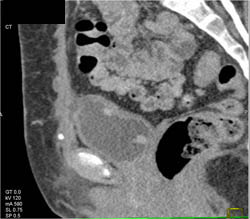

Bladder Cancer